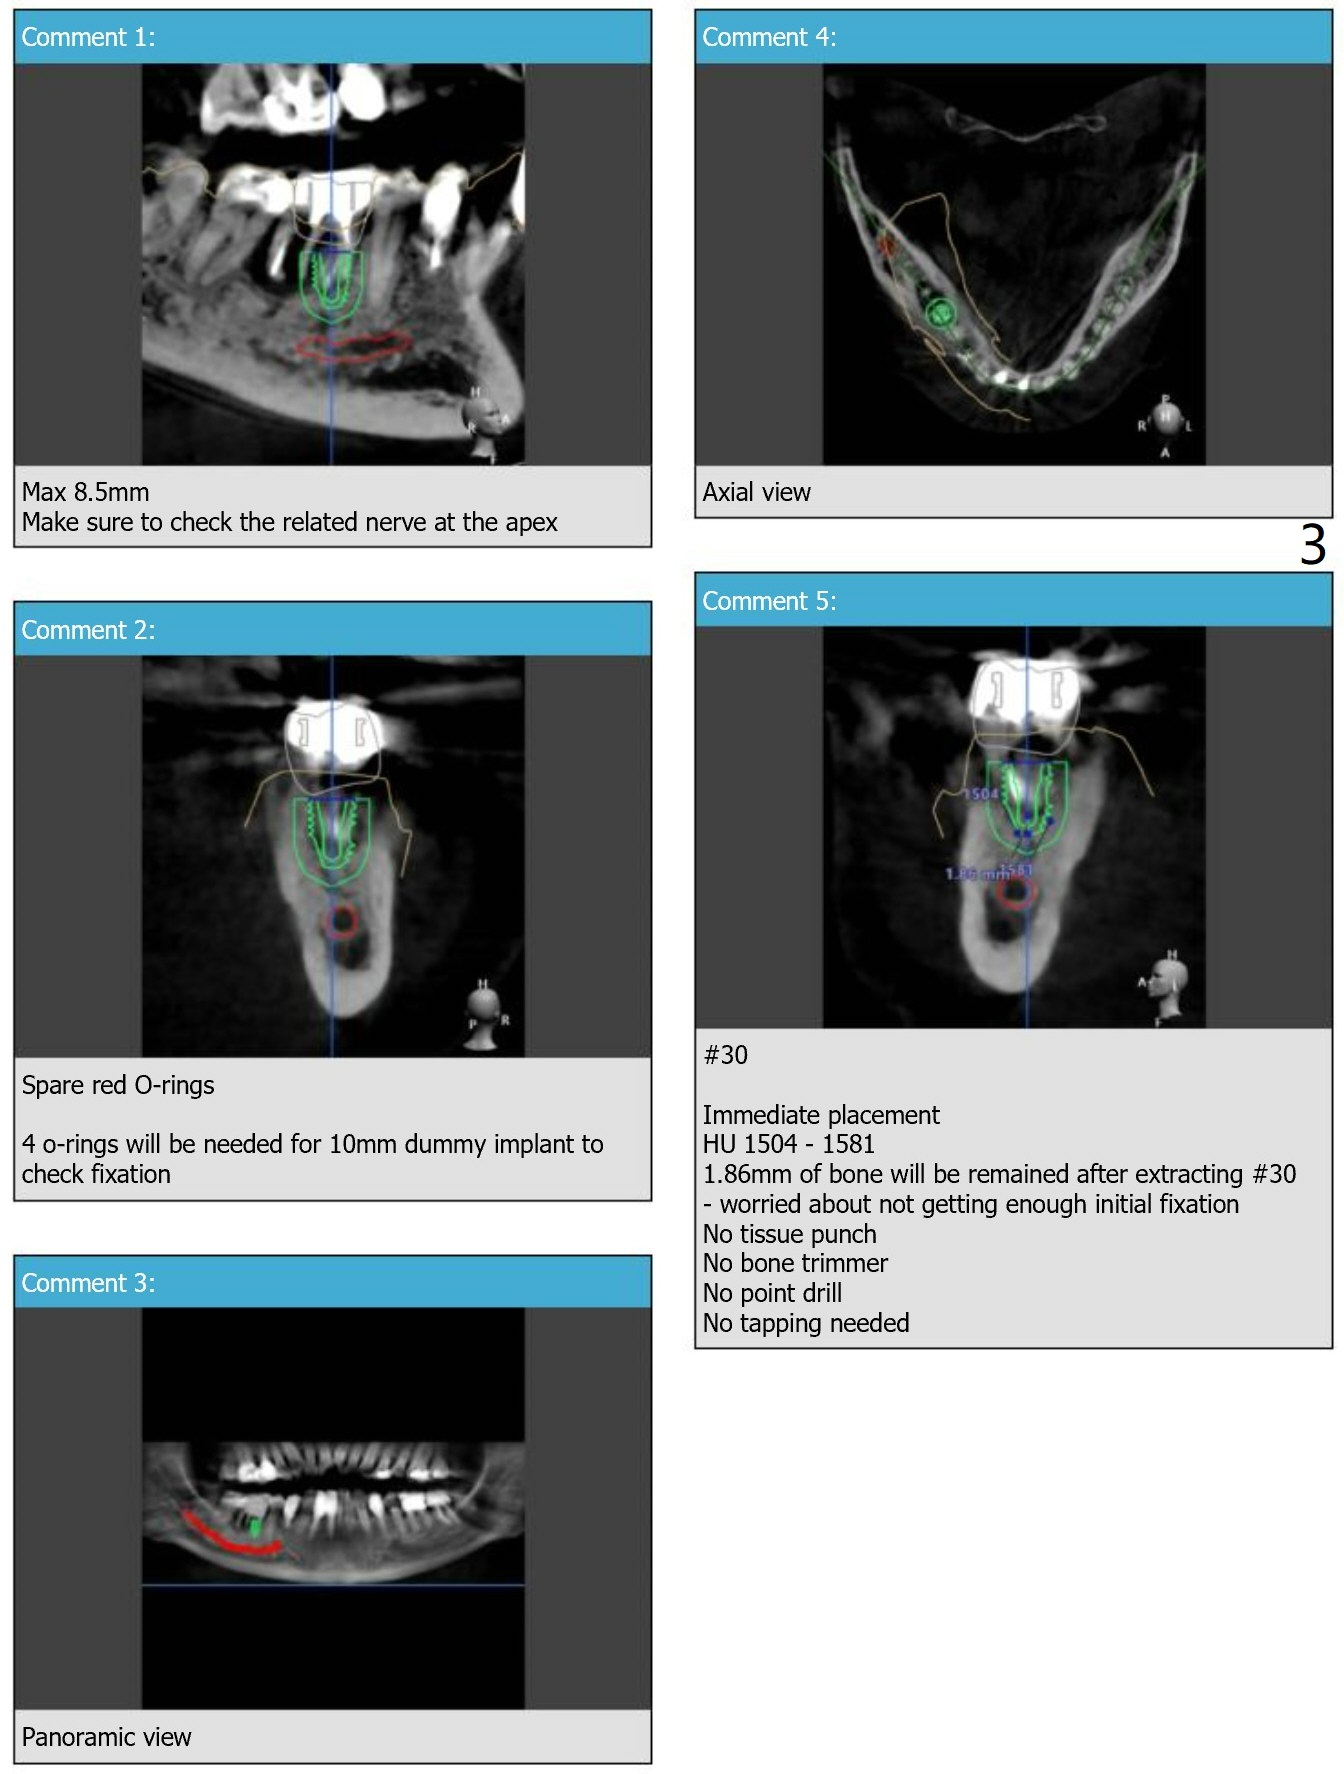

A short implant will be placed in association of a branch of the Inferior Alveolar Nerve.